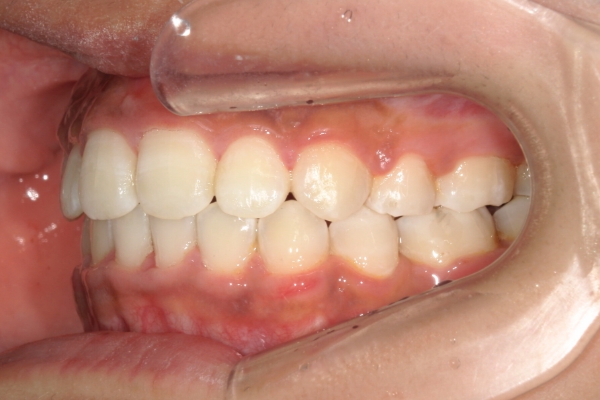

BEFORE

治療前

上顎前歯が1 cm近く前方に出ており、叢生を改善しつつ前歯を大きく引っ込めるために上下顎小臼歯の抜歯が必要と診断しました。治療では奥歯の噛み合わせのズレも整え、治療後は前歯でも奥歯でも食べ物が噛みやすくなったと、患者さまに非常に満足していただけました。